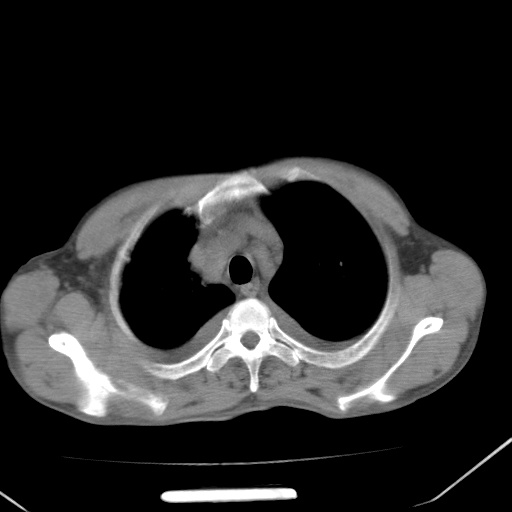

男、42岁、咯血3天。既往有甲亢、贫血、血尿蛋白尿史多年。血象:wbc:6.   中性粒:70.6%。

双肺堆成磨玻璃影,双测胸腔积液。考虑:肺水肿、间质性肺炎、真菌感染、ards、hiv感染、肺出血。

双肺野对称性磨玻璃影,分布于内中带,双侧胸水,患者有咯血。

1、间质性肺水肿;2、结合临床病史及实验室检查,考虑为肺出血肾炎综合征。    此病需与间质性炎症、粟粒性肺结核鉴别。